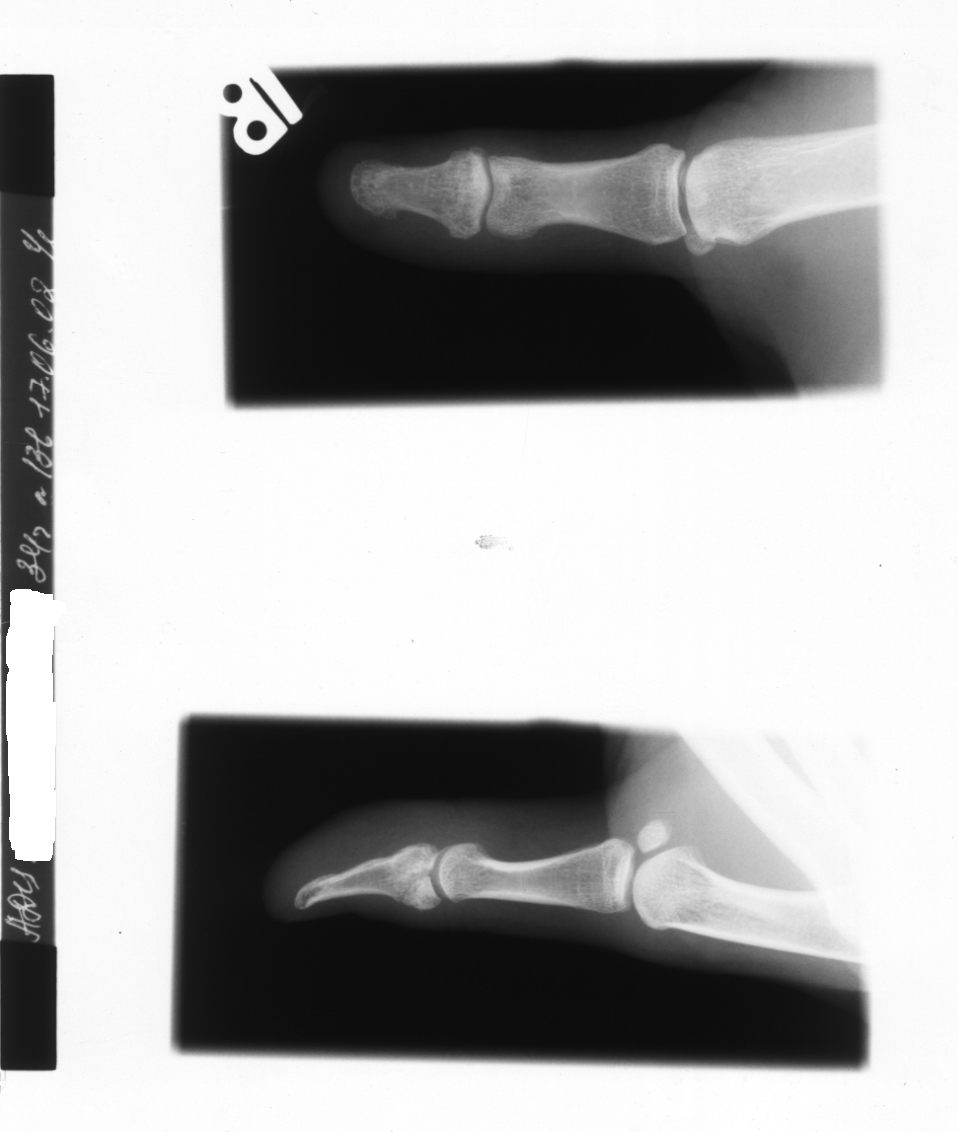

Повторный перелом пальца у волейболиста

Первый перелом - в январе 2002 года, была наложена шина на 4 недели.Повторный перелом в этом же месте - 7.06.2002 г.Вопрос: Рекомендации по лечению. Как ускорить консолидацию и можно ли пациенту сейчас с каким-то приспособлением на пальце играть в волейбол?

Первый перелом - в январе 2002 года, была наложена шина на 4 недели.Повторный перелом в этом же месте - 7.06.2002 г.Снимок через 10 дней после повторного перелома (17.06.2002г.).После первого перелома снимки не делались.В первом и во втором случае переломы - результат блокирования нападающего удара во время игры в волейбол.Сейчас пациент к пальцу лейкопластырем приматывает самодельную шину.Вопрос: Рекомендации по лечению.Как ускорить консолидацию и можно ли сейчас с каким-то приспособлением на пальце играть в волейбол?

Это отывной перелом точки прикрепления сухожилия разгибателя. Сейчас отломки расположены неплохо, можно наложить шину даже без форсированного разгибания но лучше бы проконтролировать ситуацию через пару недель. Возможно, там все-таки псевдартроз или сращение на ограниченном участке, учитывая повторный случай. Руки чешутся ввести чрескожно парочку маленьких винтов.

А играть дальше надо с шинкой, удерживающей межфаланговый сустав в максимальном разгибании.